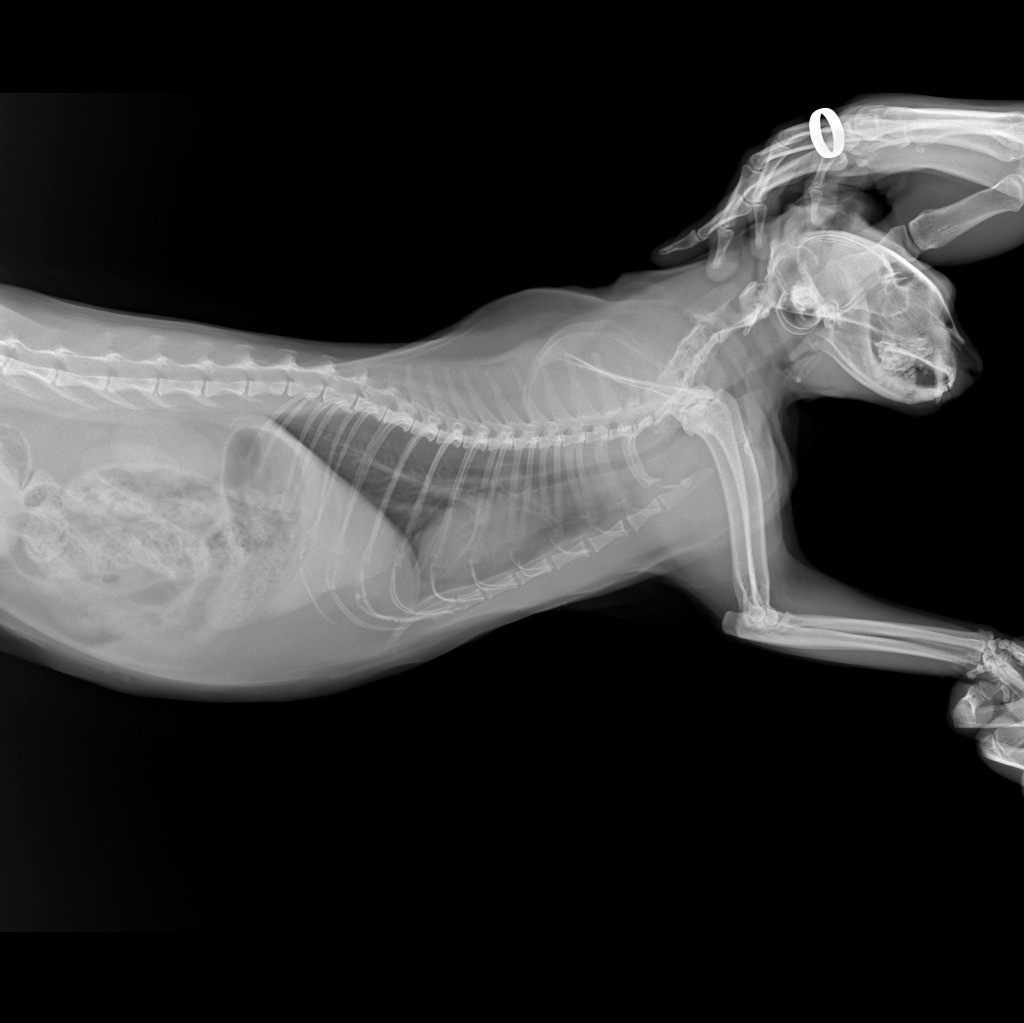

здравствуйте! Кошка начала кашлять, опустив вниз голову и высунув язык трубочкой, шерсть не выходит, длительность приступа около 30сек. Сделали рентген легких по рекомендации ветеринара, сердце проверили, в норме. Посмотрите пожалуйста рентген снимки, что по ним можно сказать?

Здравствуйте. На рентгенограммах видим усиление бронхиального рисунка, что может указывать на хронический бронхит или начало бронхиальной астмы у кошки. Учитывая характер кашля (с вытянутой шеей и языком), вероятна бронхоспазматическая реакция. Рекомендую провести бронхоскопию или хотя бы анализ мокроты (если получится получить), а также рассмотреть ингаляционное лечение (с альбутеролом или флутиказоном).

Здравствуйте. На снимках нет явных признаков новообразований или отека легких, сердце действительно в пределах нормы. Однако в дорсовентральной проекции отмечается небольшое затемнение в каудальных отделах легких это может быть связано с воспалением или астматическим компонентом. Кашель может быть реакцией на аллерген или накопление слизи. Обратитесь к ветеринарному аллергологу или продолжите диагностику по плану. Если приступы станут чаще тогда стоит срочно обсудить назначение пробного курса бронхолитиков.